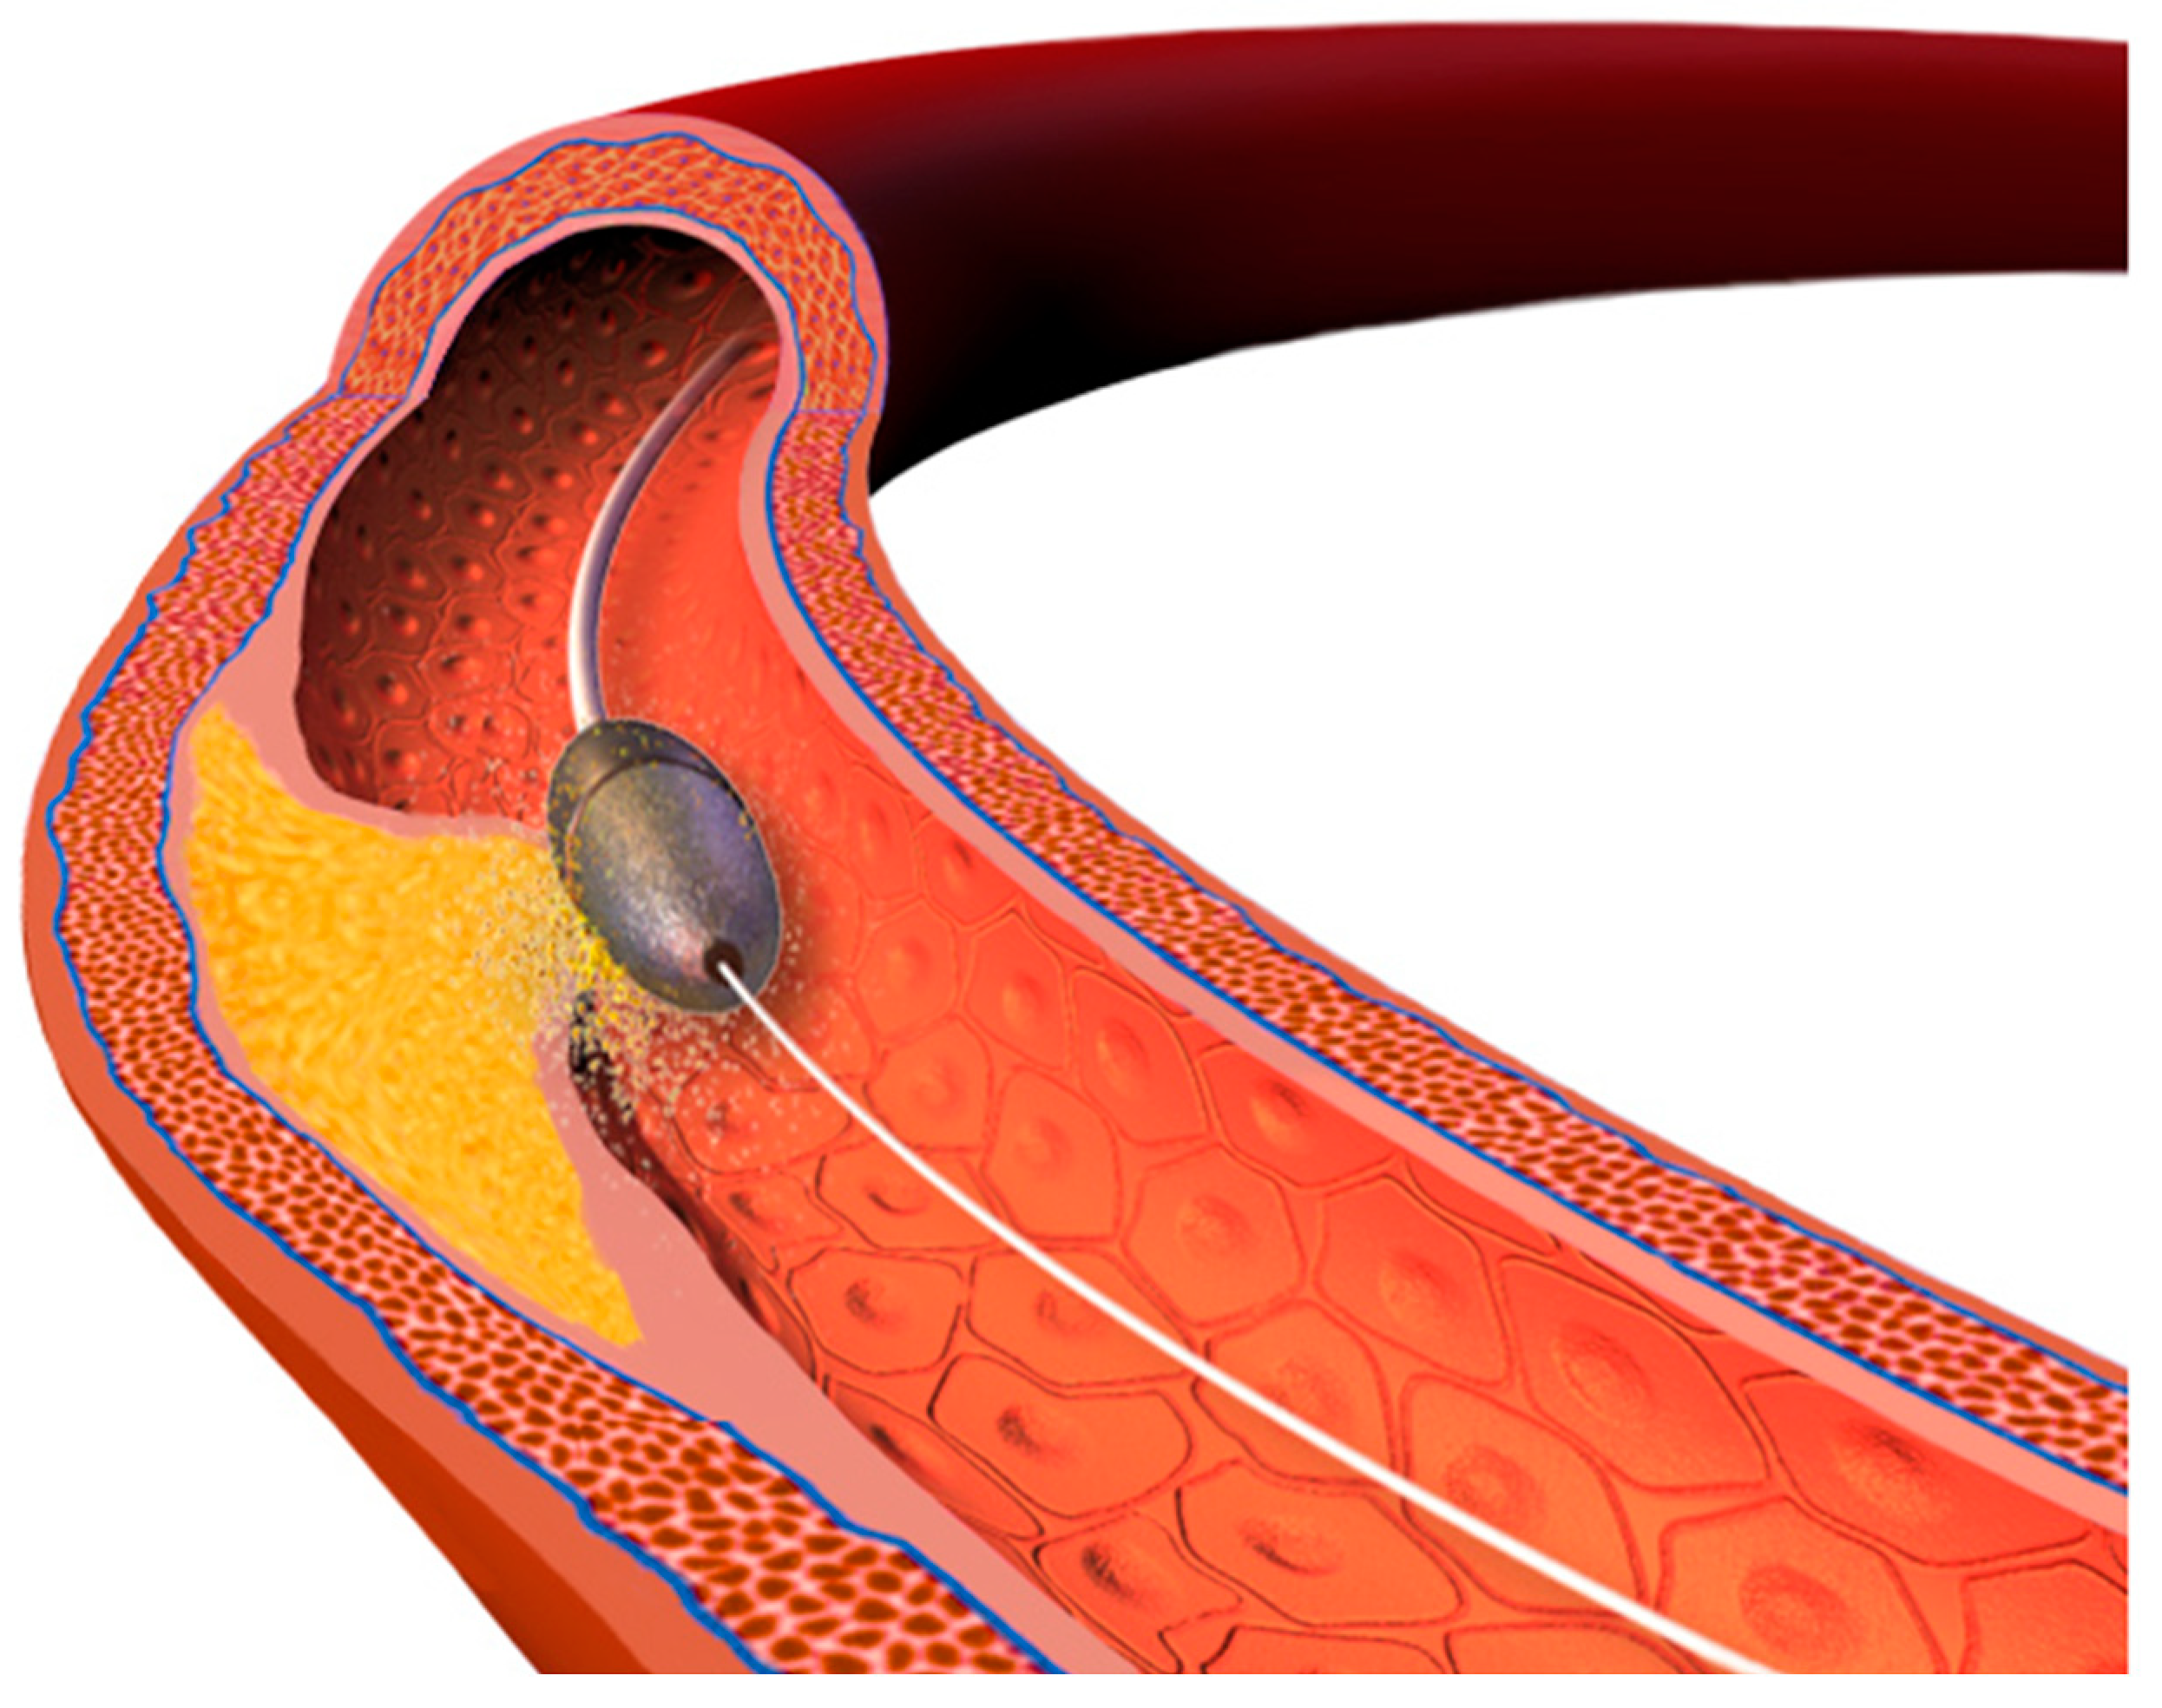

- Atherectomy techniques: rotational atherectomy (RA, rotablation) and orbital atherectomy (OA). The principle of these techniques is to ablate the calcific plaque while also creating plaque fractures and fissures.Rotational atherectomy was first described in 1987. It employs an olive-shaped burr with diamond chips embedded into it. The rotational atherectomy system consists of a console (which regulates the flow of air to the advancer, controlling burr rotation speed and also displays procedural parameters such as burr speed, duration of atherectomy, decelerations which are sudden drops in rotational speed), an advancer (which is used to control movement of the burr) and the burr itself which is introduced to the coronary vessel over a dedicated guidewire. The burr rotates at high speeds (140,000 to 180,000 rpm) and ablates the calcified tissue in a mechanism known as differential cutting (which preferentially ablates the inelastic tissue without damaging the vessel). The operator should use a pecking motion of the burr, which is a quick back and forth movement of the burr to the lesion and back. Decelerations in burr rotational speed should be avoided in order to prevent the burr stall which is serious complication (a situation in which the burr is stuck in the lesion and can no longer be moved or rotated). The particles of debris are <5 μm in diameter and can pass to the systemic circulation without causing distal embolization, however, some considerations are important to prevent the no-flow or slow-flow phenomenon (short burr runs, pauses between runs, appropriate rotational speed, avoidance of decelerations, appropriate pharmacotherapy, i.e., verapamil, nitrates, proper periprocedural anticoagulation). The burrs come in different sizes (from 1.25 mm up to 2.5 mm) to make it suitable for different vessel diameters (burr size should be <0.7 of a reference vessel diameter). PREPARE-CALC (patients were randomized to a lesion modification with use of either RA or cutting/scoring balloons) and ROTAXUS (randomization to groups with RA followed by stenting or stenting without RA) trials indicated that RA before stent implantation is feasible and effective nearly in all patients with heavily calcified lesions [39,40]. A schematic representation of the RA burr is shown in Figure 3.Orbital atherectomy uses two physical mechanisms: differential sanding and centrifugal forces. The crown rotates eccentrically (off-center), creating an “orbital” motion as it spins around the catheter shaft. Compared to RA, there is only one size of the crown, but use of different speed settings makes it suitable for different vessel sizes (the range of the orbital motion is higher with higher speeds). Two speed settings are available; low speed (80,000 rpm) is often used for the first pass, while the higher speed (120,000 rpm) can be utilized in certain lesions, especially in vessels with a larger diameter. Contrary to RA, OA works bidirectionally both when it is advanced and retracted. The ORBIT II trial has proved the safety of the procedure by indicating a low rate of adverse ischemic events [41]. A large, randomized ECLIPSE trial (OA vessel preparation compared with high-pressure balloons angioplasty and/or cutting balloons) is ongoing [42].